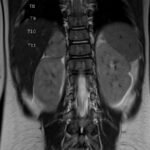

Pediatric neuroblastoma is famously characterized by an abdominal mass in a toddler with “raccoon eyes,” Horner syndrome, and/or opsoclonus myoclonus. However, rare cases may present with non-discrete symptoms and signs which create challenges for timely diagnosis. This case depicts a toddler with bulbar symptoms, including bilateral ptosis, dysphagia, drooling, head tilt and ataxia in a post-viral course mimicking other neurologic diagnoses, including myasthenia gravis. Magnetic resonance imaging (MRI) of the brain and spine uncovered a right adrenal mass along with heterogenous enhancement in multiple vertebral bodies and the clivus, consistent with metastatic disease. A diagnosis of neuroblastoma was confirmed with elevated homovanillic acid (HMA) and vanillylmandelic acid (VMA) levels and adrenal biopsy. The patient was treated with plasmapheresis for suspected paraneoplastic neurological syndrome and subsequent chemotherapy. In this case presentation, we review neurologic syndromes causing acute-onset pediatric bulbar weakness along with the patient’s key MRI findings.